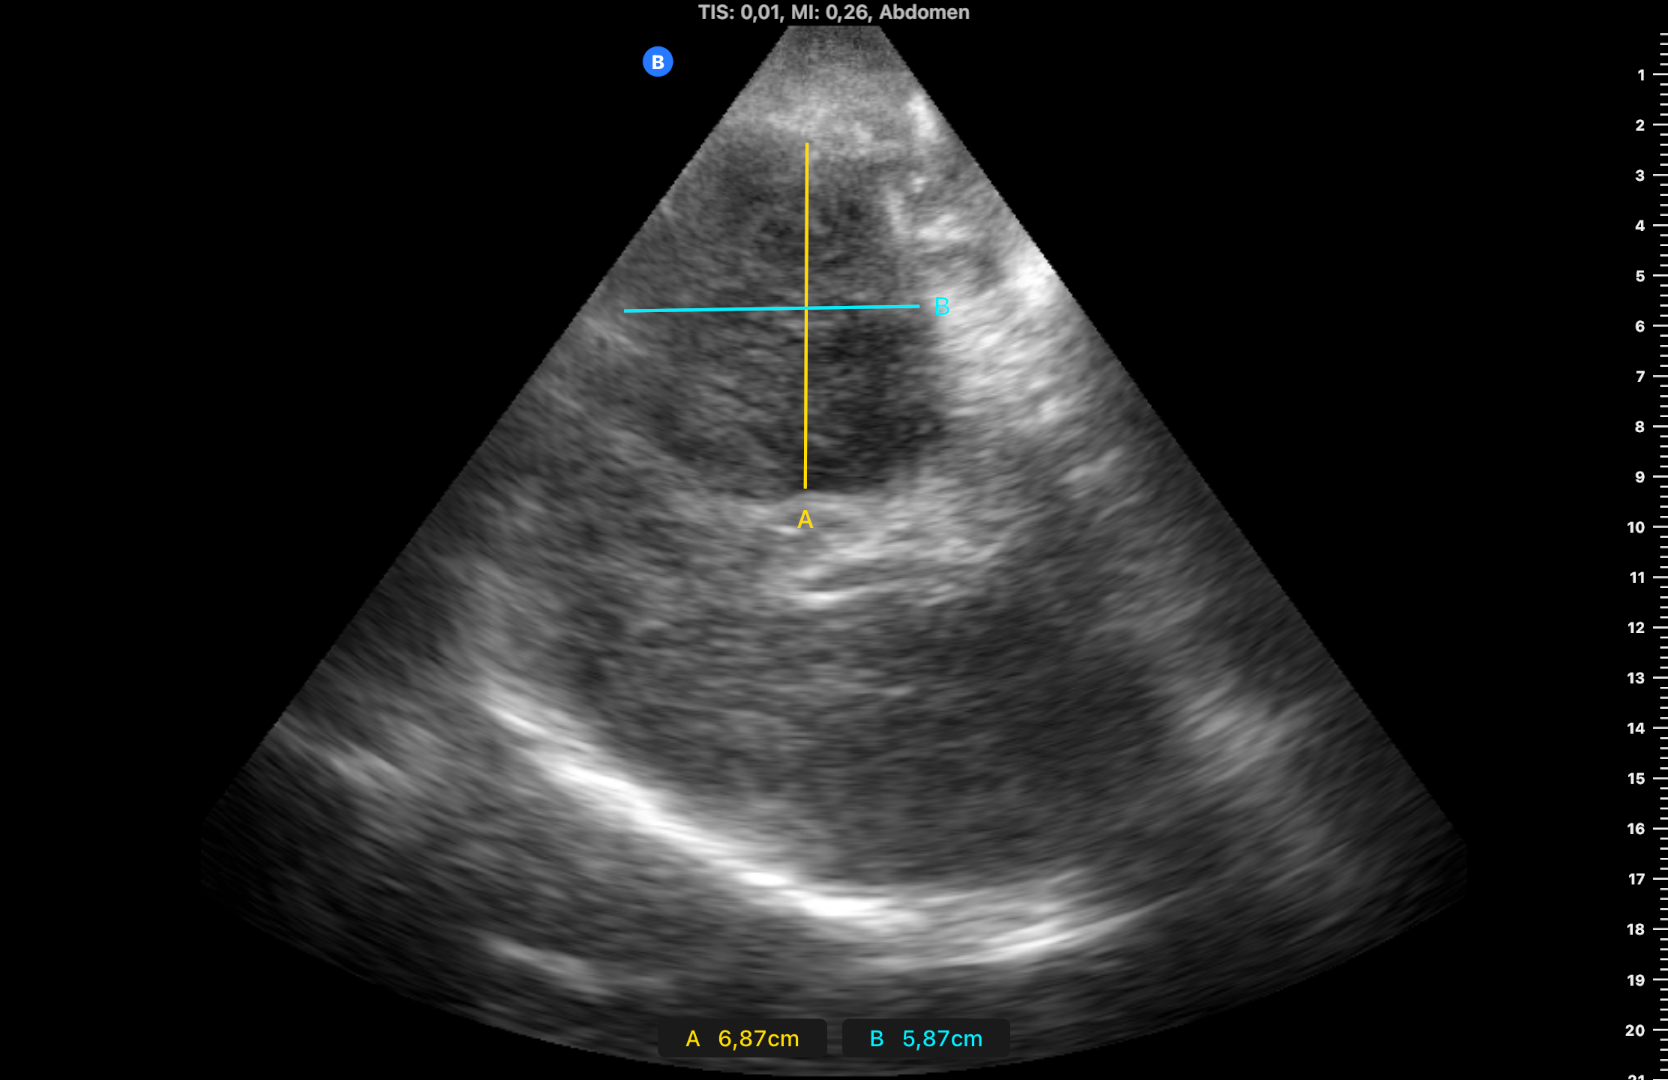

Ocupación de espacio con trombo venoso ecogénico desde poplítea hasta tercio superior, así como safenas externa e interna (imagen 2 femoral profunda e imagen 3 safena mayor). Lesión isoecogénica en segmentos hepáticos V/VI de 6,65 x 5,87 cm (imagen 4).

Masa hepática sospechosa de malignidad. TVP MID secundario a lo previo que se confirma por cirugía vascular. Diagnóstico diferencial con metástasis hepáticas y estirpe hepatobiliar.

En la analítica destaca CA 19-9 >12000 y en TAC body «masa hepática con signos de infiltración (hepatocarcinoma vs colangiocarcinoma) sin poder descartar metástasis». Eco BAG: compatible con neoplasia biliar.